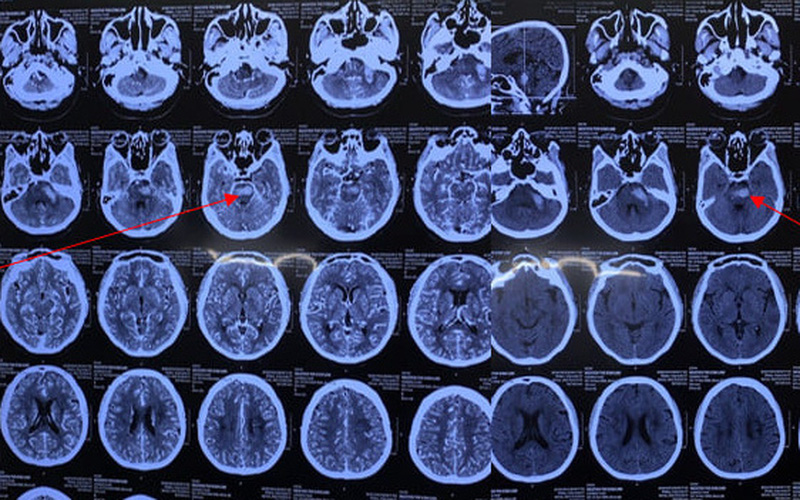

Đây là một trường hợp người bệnh bị nhồi máu não vừa được Bệnh viện Việt Nam – Thụy Điển Uông Bí (Quảng Ninh) tiếp nhận điều trị.

Sau chích máu 20 phút, người bệnh được đưa đến cấp cứu tại Bệnh viện Việt Nam – Thụy Điển Uông Bí và được chẩn đoán nhồi máu não.

Đột quỵ não hay còn gọi là tai biến mạch máu não là tình trạng một phần não bị hư hại đột ngột do mất nguồn máu nuôi dưỡng khi mạch máu não bị tắc nghẽn hoặc bị vỡ. Đột quỵ não có tỷ lệ tử vong rất cao, để lại những di chứng rất nặng nề cho người bệnh, nhẹ thì tê hoặc yếu tay chân, méo miệng, nói khó. Nếu nặng có thể liệt hoàn toàn nửa người hoặc toàn thân, hôn mê, thậm chí tử vong.